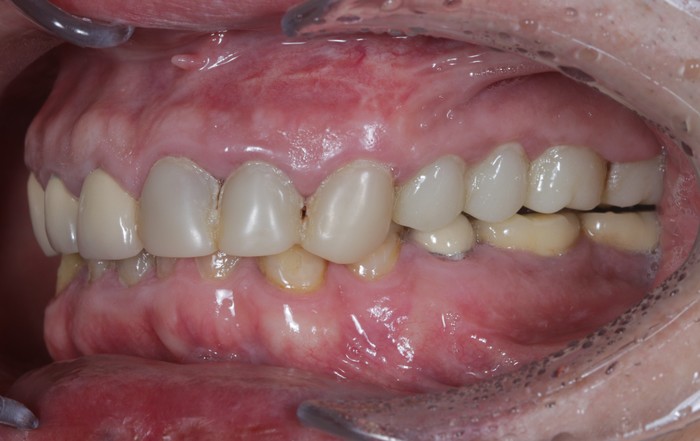

Вот пример того, когда пациент пренебрёг данным правилом:

Мужчине были установлены и спротезированы (временными коронками) имплантаты в другой клинике. После этого он пропал на несколько лет, не закончив полностью свое лечение. Явился лишь тогда, когда почувствовал «дискомфорт».

Кроме несостоятельности старых коронок и пломб, патологической стираемости зубов и т.д. - все эти годы сильно страдала гигиена.